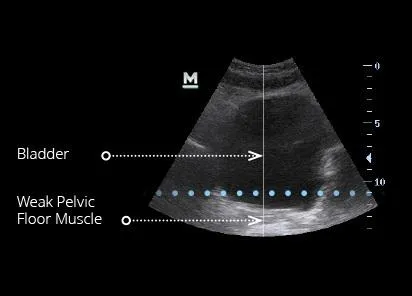

The pelvic floor muscles play a crucial role in supporting the bladder and maintaining continence. They help keep the urethra closed during daily activities — preventing leaks when you cough, laugh, sneeze, or exercise.

When these muscles weaken, it becomes harder to control bladder pressure, leading to stress or urge incontinence. Strengthening them through EMSELLA treatments improves muscle tone, coordination, and bladder support — helping reduce leaks naturally, comfortably, and without medication.